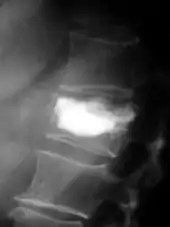

Pour le diagnostic initial, la radio X classique a une importance centrale. L'indication pour des projections sur deux plans est toujours donnée en cas de soupçon de tumeur osseuse[87]. Les métastases ostéolytiques sont caractérisées par une perte de densité osseuse. Ceci se reconnaît sur la radio par un noircissement plus élevé, en raison de la plus grande transparence aux rayons X. Inversement, les métastases ostéocondensantes présentent à cause de la plus grande densité osseuse un noircissement inférieur. Les métastases ostéolytiques sur la colonne vertébrale sont nettement plus difficiles à reconnaître : seulement quand environ 50 % de la densité totale de l'os a disparu[87].

Scanner d'une métastase ostéocondensante dans l'os du crâne d'un patient souffrant d'un carcinome de la prostate. On reconnaît clairement l'extension de la métastase au-delà des limites initiales de l’os.

Par comparaison, scanner de métastases ostéolytiques dans l'os du crâne d'une patiente souffrant d'un cancer du sein. On distingue une ostéolyse plus grande sur le front, et plusieurs plus petites.